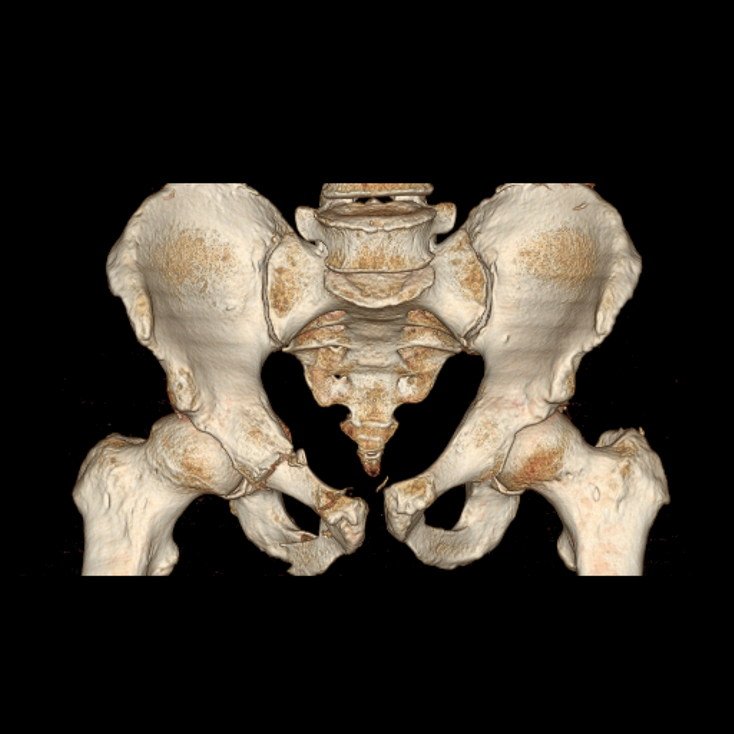

3D CT Hip

3D CT Pelvis